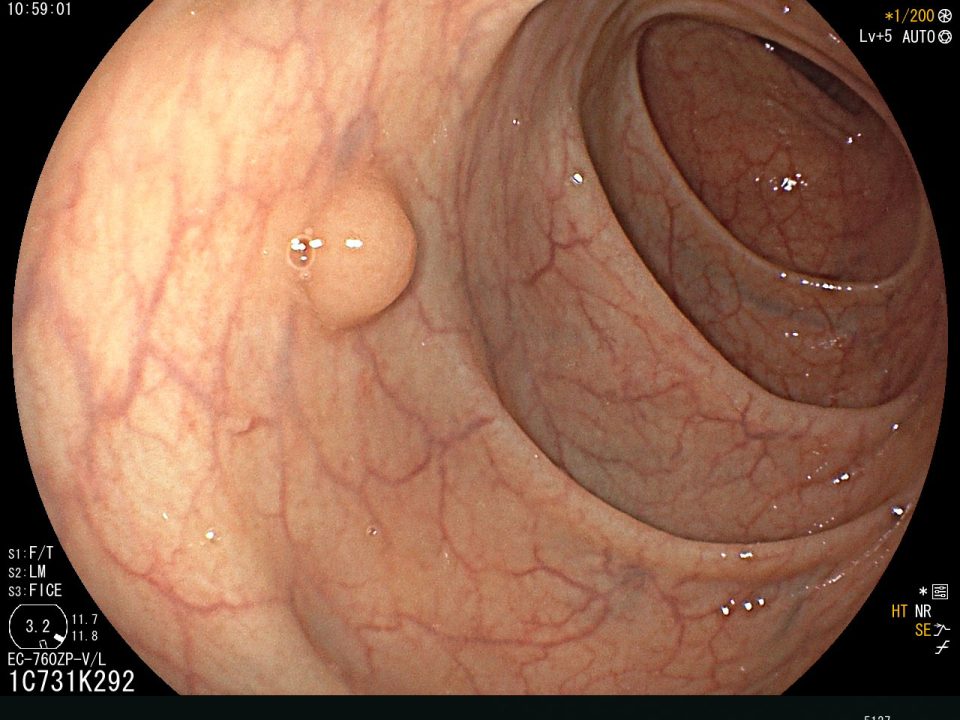

Pólipo de Colón

El Cáncer Colorectal afortunadamente tarda bastante tiempo en alcanzar etapas avanzadas y un porcentaje elevado de casos presenta lesiones previas benignas (pólipos) que con la evolución se transforman en cáncer, primero precoz y luego avanzado; sin embargo, el concepto es que estas lesiones premalignas pueden ser detectadas y extirpadas (polipectomìa) en etapas iniciales evitando así el desarrollo del cáncer.

En los últimos años se ha demostrado claramente que el número de personas que desarrollan y mueren por Cáncer Colorectal puede reducirse de manera drástica mediante una detección y vigilancia adecuadas, de manera que el tamizaje (screening) de ésta enfermedad es efectivo y debe recomendarse. La detección precoz o screening del cáncer en un sentido amplio es una forma de prevención, existen múltiples estudios que indican una reducción de la incidencia de esta enfermedad como resultado de la detección y resección de los pólipos adenomatosos.

Existen varios test de detección precoz del Cáncer Colorectal como los Test Inmunoquímicos de sangre oculta en heces (Hb humana), marcadores de ADN fecal, Rx enema baritado de colon a doble contraste, colonoscopia virtual, pero la realización de una Videocolonoscopia total sigue siendo el Gold Standard para la detección del Cáncer Colorectal.